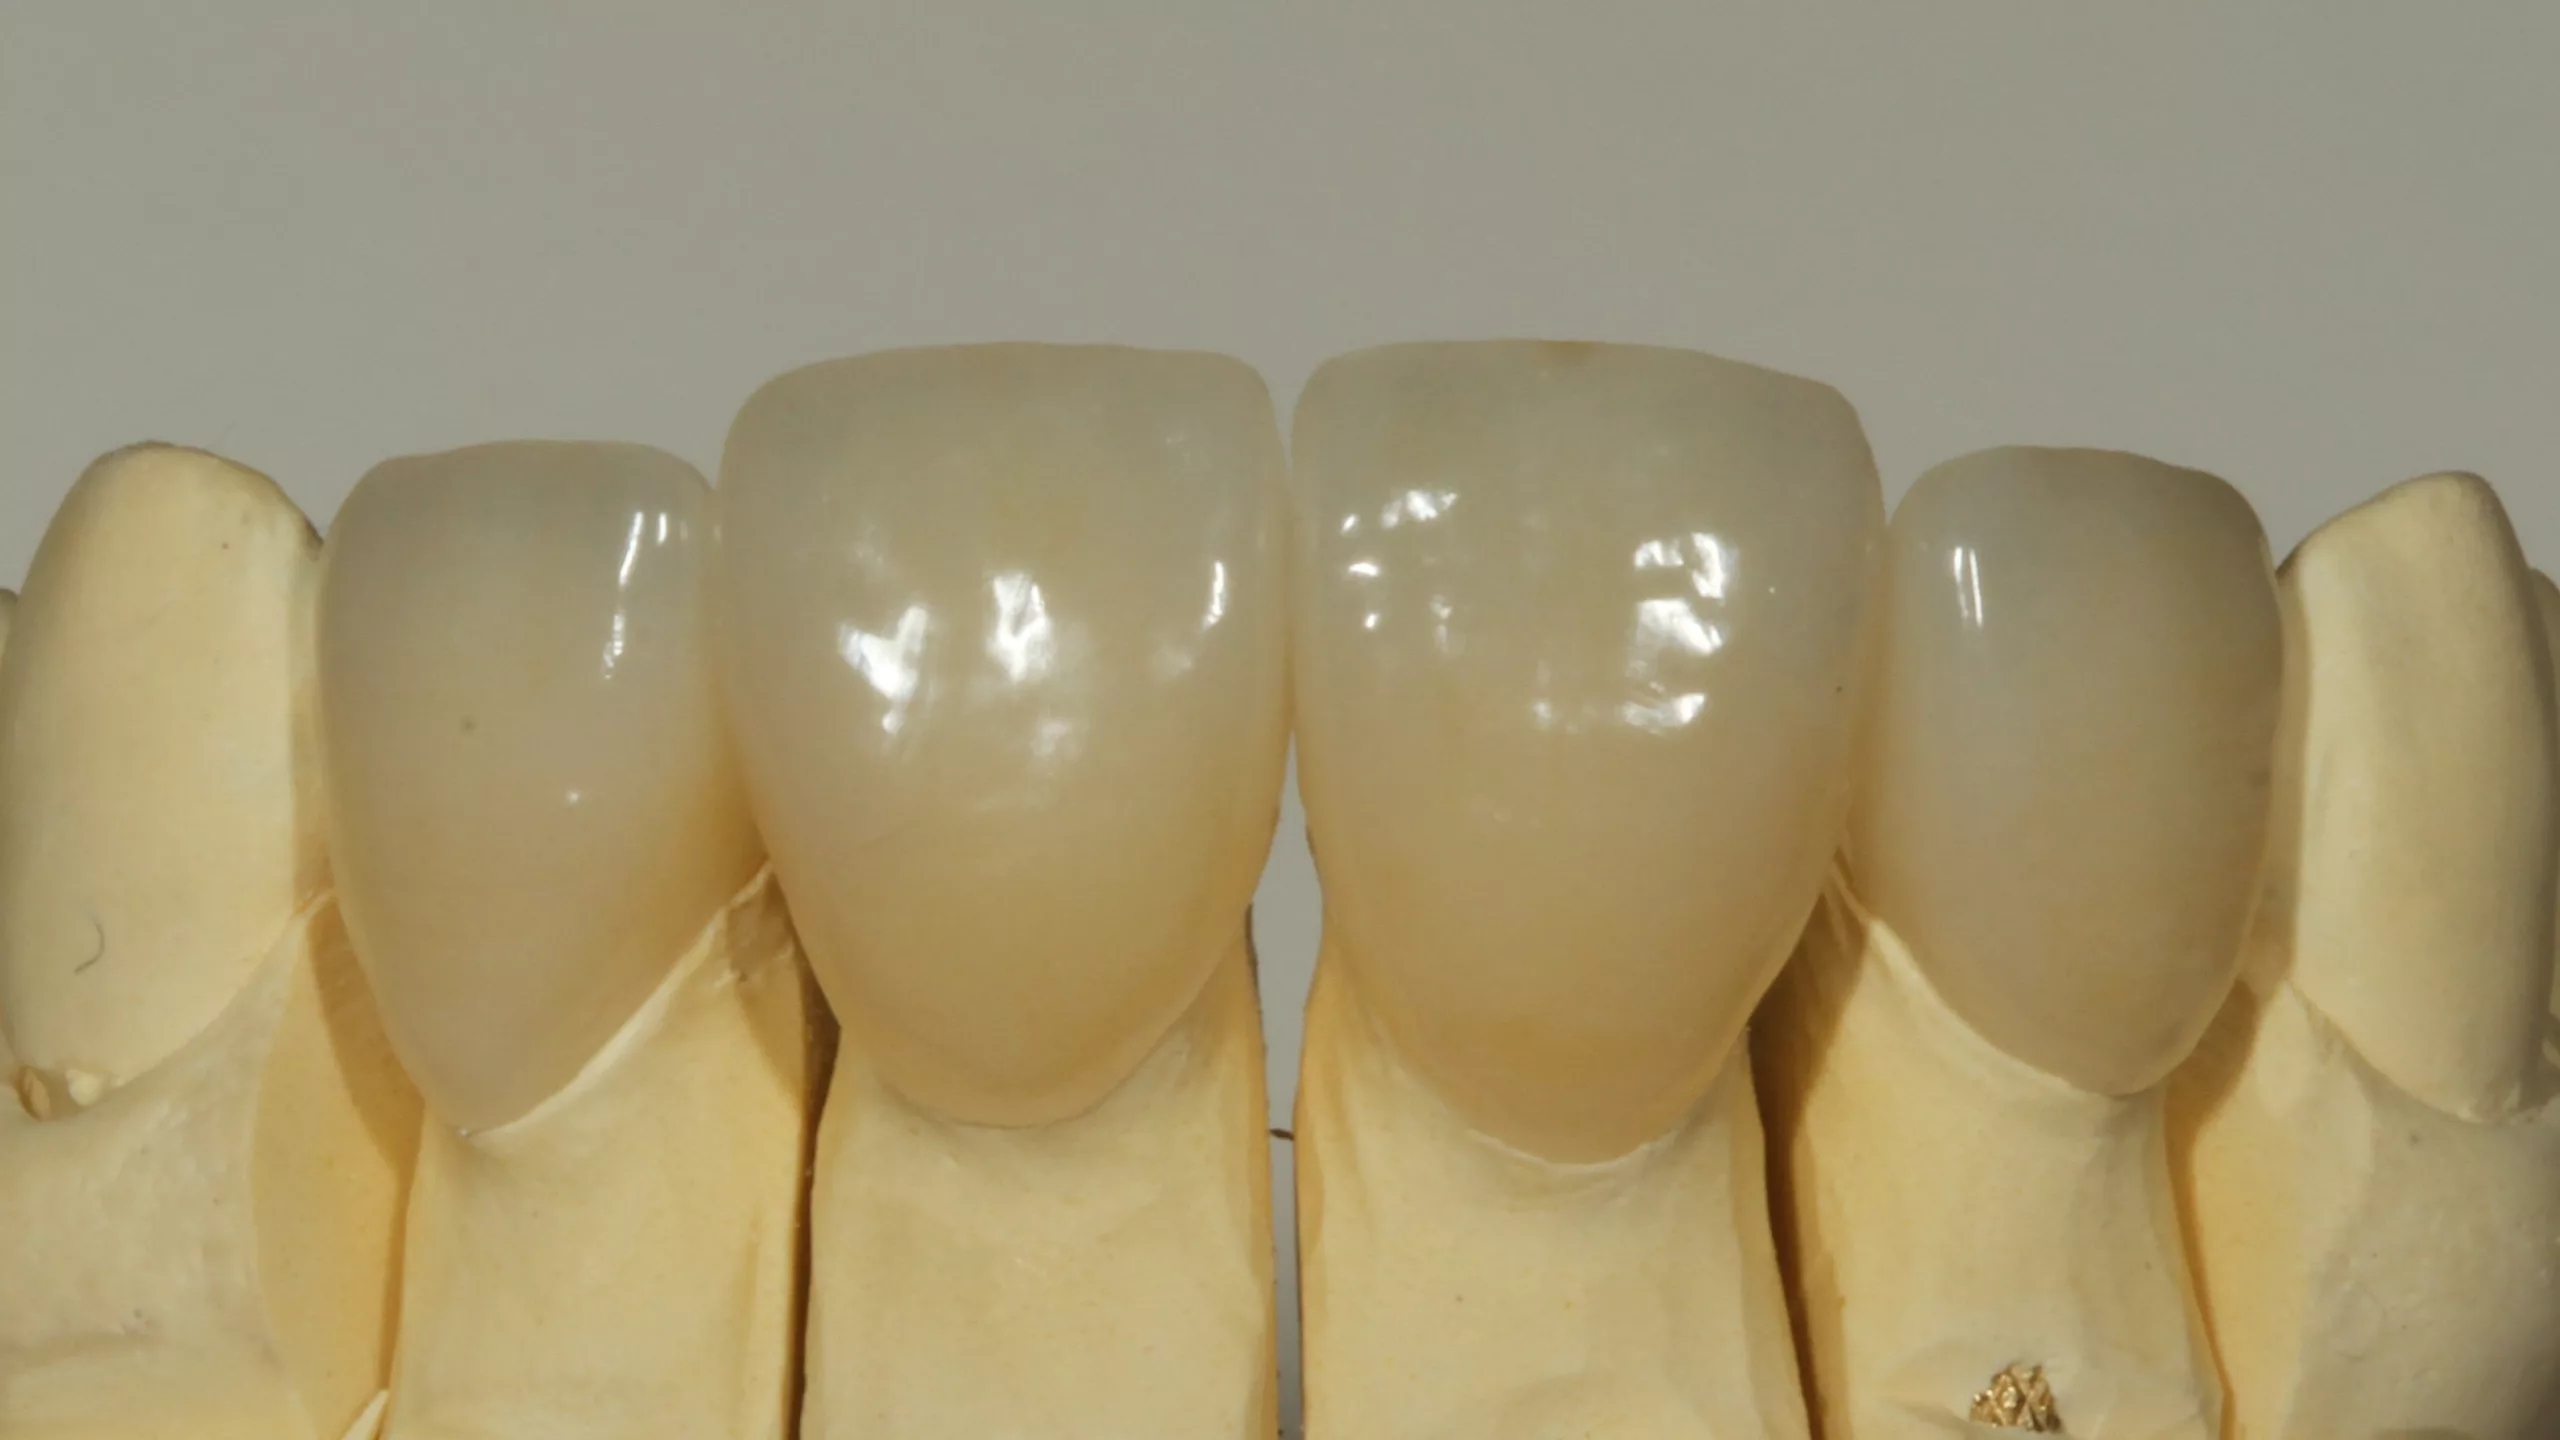

Bei der 55-jährigen Patientin bestand der Wunsch nach einer ästhetischen Neuversorgung ihrer Frontzahnsituation (Abb. 29 und 30). Die Zähne 11 und 22 waren wurzelkanalbehandelt, alle Schneidezähne wiesen ältere, große, farblich nicht mehr passende Kompositversorgungen auf. Die Neuversorgung wurde aufgrund der Stabilität und der besseren Abdeckung verfärbter Zahnbereiche aus einem monolithischen Zirkonmaterial gefertigt, die labial additiv verblendet wurden (Abb. 31 und 32).